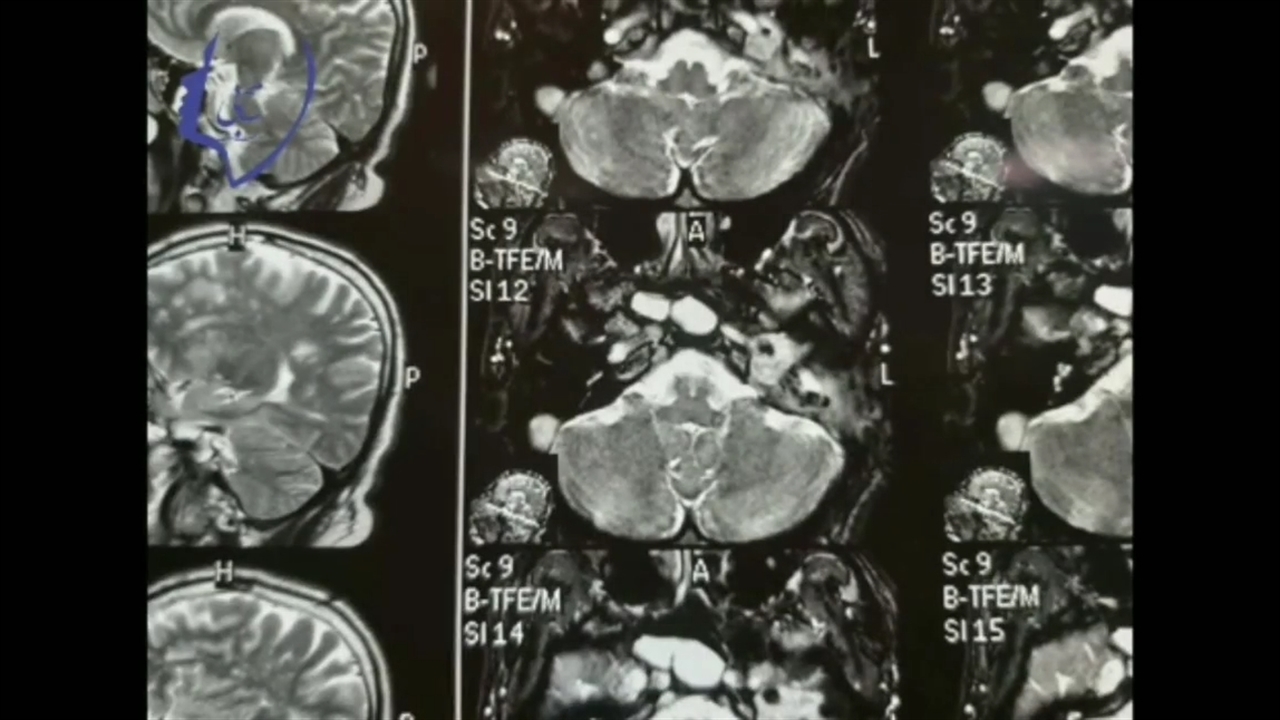

پخش صدا تومور یا عفونت اشتراکگذاری لیست پخش ۰ نظر ۰ نظر دانلود دانلود ویدیو دانلود کیفیت 480p ۴.۰۴ مگابایت دانلود کیفیت 360p ۲.۹۴ مگابایت دانلود کیفیت 240p ۱.۹۷ مگابایت دانلود کیفیت 144p ۱.۳۲ مگابایت گزارش تخلف بیشتر گزینههای بیشتر لیست پخش لایکها گزارش تخلف ۰ لایک دکتر صالح محبی- فلوشیپ جراحی قاعده جمجمه از آلمان منتشر شده در تاریخ ۱۴۰۰/۰۵/۱۳ این کانال دنبال شد دنبال کردهاید دنبال کردن این کانال دنبال کردن تومور گوش یا عفونت گوشhttps://salehmohebi.ir/ ادامه نظرات لبخند لبخند لغو ثبت نظری برای نمایش وجود ندارد.